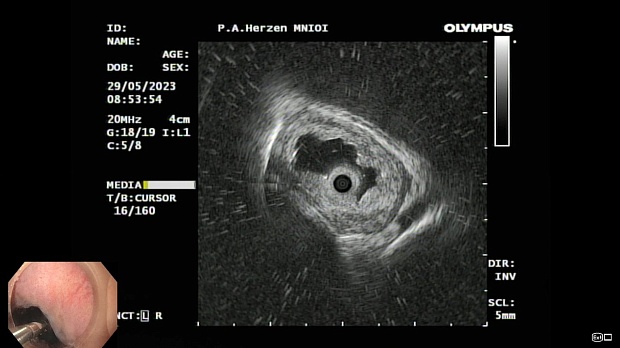

Иллюстрация №1: Эндофото. Сидероз нижней трети пищевода, осмотр в белом свете

Иллюстрация №3: Эндофото. Сидероз нижней трети пищевода, эндоскопическая ультрасонография

Согласно полученным данным - в среднегрудном и нижнегрудном отделах пищевода определялась проксимальная граница плоских неправильной формы поверхностных рубцов суммарной протяженностью до 8,0 см. На этом фоне в зонах поверхностных рубцов по задней полуокружности визуализировались участки гиперпигментации в темный цвет (Рис. 1). При исследовании в режиме Dual Focus было отмечено наличие мелких (до 0,001 см) черно-коричневых включений, расположенных субэпителиально - в строме слизистой оболочки, сливания их в единый конгломерат не определялось (Рис. 2). При эндосонографии с применением минидатчика с частотой сканирования 20МГц выявлено, что все слои стенки четко дифференцируются, не утолщены, в слизистой оболочки визуализированы мелких гиперэхогенные включения с эхотенями (Рис. 3).

В пищеводе в шейном его отделе на уровне 16 см от резцов циркулярно визуализированы единичные синюшные флебоэктазии размерами до 0.5 см. Дистальнее пищевод визуально не изменен до уровня 28 см от резцов, где определяется проксимальная граница плоских неправильной формы поверхностных рубцов, распространяющихся до уровня 36 см от резцов. На этом фоне в зонах поверхностных рубцов по задней полуокружности визуализированы участки гиперпигментации в черно-коричнеый цвет. При осмотре в режиме Near Focus с увеличением - между зон пигментации определяются расширенные капилляры типа II по Inoue-классификации. При биопсии отмечена десквамация плоского эпителия, визуализированы мелкие черно-коричневые включения в строме слизистой оболочки, размеры их до 0,001 см, сливания их в единый конгломерат не отмечается. При эндосонографии с датчиком 20Мгц в исследуемой зоне в слизистой оболочке определяются гиперэхогенные включения, в то время как в подслизистом слое - зоны со сниженной эхогенностью. При биопсии отмечается уплотнение ткани, однако истинной фрагментации не определяется. Уровень Z-линии совпадает с уровнем анатомического кардиоэзофагеального перехода. Розетка кардии эластичная, смыкается не полностью, расположена на уровне пищеводного отверстия диафрагмы.

Заключение: Эндоскопическая и эндосонографическая картина трудна для трактовки: следует дифференцировать сидероз слизистой оболочки пищевода на фоне постэрозивных рубцов и меланоз пищевода